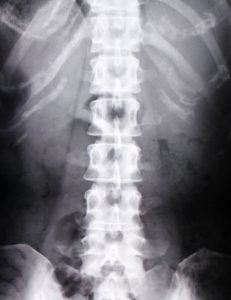

☑老化や骨の変形で痛みが起きる

☑画像検査で痛みの原因が分かる

☑椎間板ヘルニアで神経が圧迫されると腰痛になる